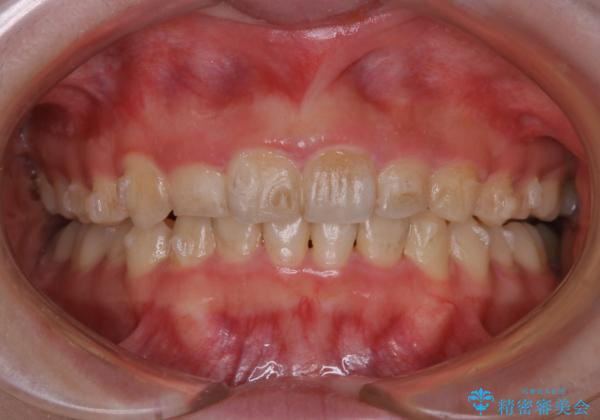

インビザライン中にステインの除去

- インビザラインでのマウスピース矯正中の方で、歯の表面のステインをきれいに取りたいとのことでした。PMTC60分コースを行いました。

PMTC(保険外治療)は、毎日の歯磨きで落としきれない汚れや、コーヒ、紅茶・タバコのヤニなどの着色も除去します。目には見えない歯と歯の間・歯肉の境目・インビザライン中はアタッチメント周囲などに残っているプラーク(歯垢)もしっかり取り除きます。PMTCでは専門的な機械や材料を使用して、徹底的に汚れを除去するため、虫歯・歯周病・口臭予防などにつながります。

またPMTCを行うことで、ご自身本来の歯の色になり自然な明るさになります。

口元が自然な明るさになることで、より清潔感のある印象になるため結婚式・行事やイベント前などにもPMTCを行うはおすすめです。